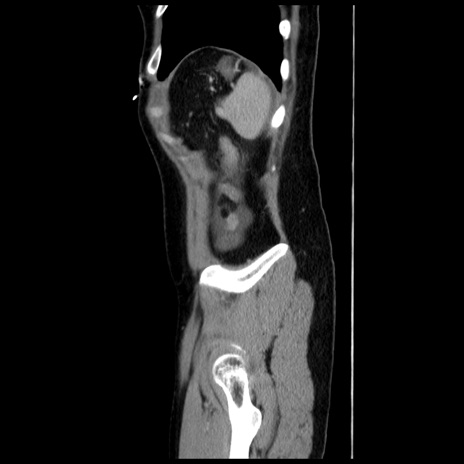

症例10(矢状断像)

【症例】 50歳代女性

【主訴】 腹痛

【現病歴】前日生レバーを食べた。今朝に排便あり。 昼前に突然発症の腹痛を生じ、当院救急外来を受診した。

【既往歴】 子宮筋腫にてで子宮全摘後

【身体所見】 意識清明、腹部:平坦、軟、下腹部やや左を中心に圧痛・反跳痛あり、筋性防御あり

【データ】WBC 7800、CRP 0.07